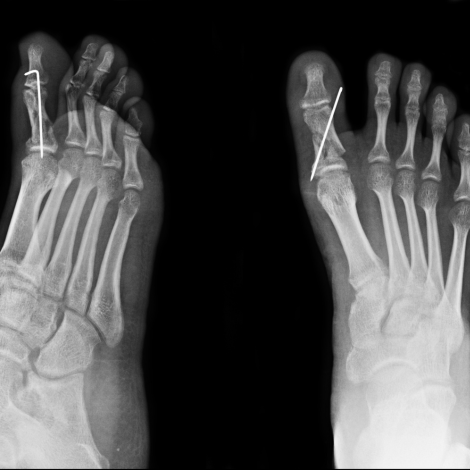

Foot X-ray

If your doctor suspects that your foot pain is being caused by a fracture, he or she will prescribe an X-ray to see the bone and look for signs of a crack or break. An X-ray can also tell your doctor if the bone has been affected by an infection, arthritis, or other bone disease. If you have suffered an injury, an X- ray lets your doctor locate pieces of glass, metal, or other foreign objects that can be lodged in the wound